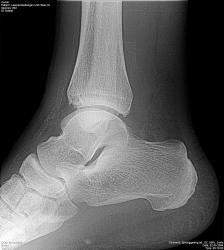

Для диагностики пневмонии, синуситов, травм и переломов, заболеваний суставов и позвоночника необходим рентген. Мы используем современный цифровой рентген, снимки выдаются сразу на месте и распечатываются на специальной фотобумаге. Вас осмотрит врач, установит диагноз, заберет анализы и назначит лечение перелома, выполнит необходимые инъекции, сделает гипс. Мифы и правда о рентгене на дому!